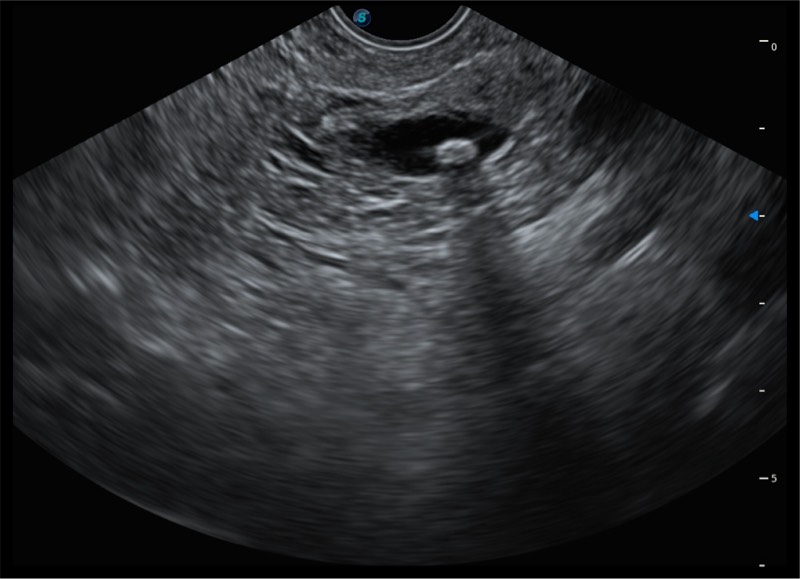

基于二十年的超声技术积累,银河集团官网提供了最新一代的独立超声主机,在提供高质量图像的同时满足多学科使用。具备常见多普勒技术并提供弹性成像、声学造影等高端影像技术。新一代传感器具有更强的抗干扰能力并减少图像伪影。

150°超声扫描角度

4-12MHZ宽频输出